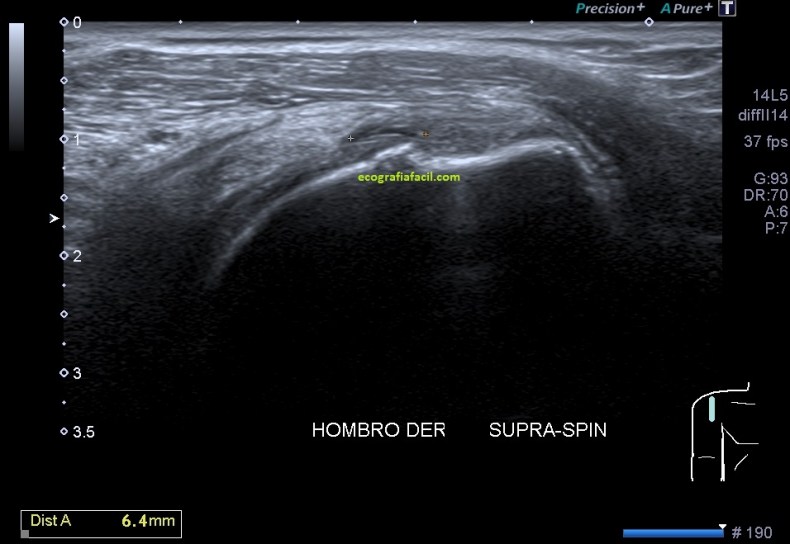

En la imagen 2 observa el corte longitudinal de un tendón supraespinoso donde ves la medida de una imagen alargada, anecoica que ocupa parte del tendón, típico aspecto de la rotura en ojal del tendón sin que éste tenga el signo de la rueda pinchada…y dirás tu, ¿y eso qué es?